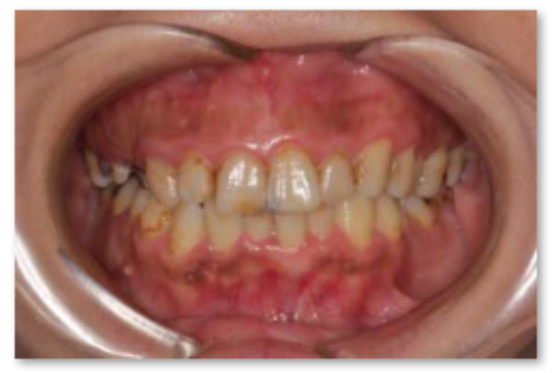

主訴は「全ての歯を綺麗に治したい」とのことで来院されました。診断の結果、複合的な問題が見つかり、歯周病治療、矯正治療等複数の治療を約3年ほど順番に進めていきました。最終的には歯の色味も回復させることができ、患者さんにも満足していただけました。

| 患者 | 45歳 女性 |

|---|---|

| 主訴 | 前歯が取れた。 |

| 診断 | このケースはかなりひどい叢生があり、矯正治療が必須であると説明。 |

| 治療内容 | 左上5は保存不可能のため、右上より5を左上に移植 矯正終了後補綴治療 |

| 治療期間 | 約3年半 |

| 費用 | 200万円 |